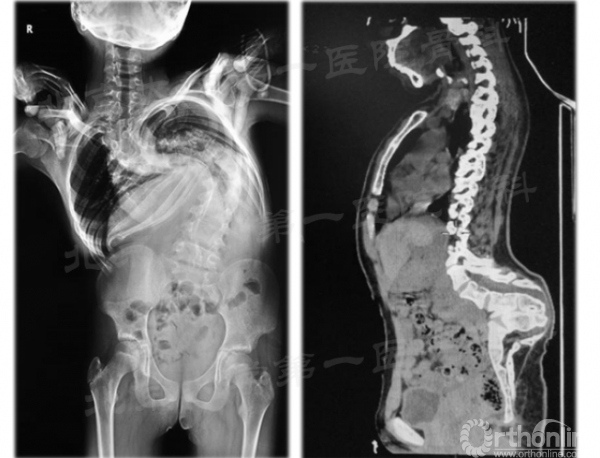

典型病例1

21岁女性,早发型脊柱侧后凸畸形伴限制性通气功能障碍。15年前出现脊柱侧弯,之后进行性加重, 运动耐量欠佳,跑步后胸闷明显,无神经症状。牵引2周后身高增加14cm,牵引第3周时出现右下肢力弱,及时放松牵引后肌力恢复。 牵引后冠状面矫形率为41.4%,矫形术后冠状面总矫形率60.0% 。牵引后矢状面矫形率为55.5%,矫形术后冠状面总矫形率66.4%。